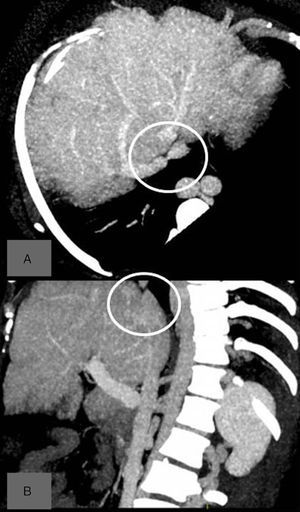

En una ecografía abdominal de control en 2015 se objetivó una imagen compatible con un CHC en el segmento 6 hepático de 2,7cm, confirmada mediante TC abdominal (fig. 1A). Ante una paciente con un CHC y signos de hipertensión portal (trombocitopenia y antecedente de ascitis) se planteó trasplante hepático5. Sin embargo, en la TC abdominal se objetivó que las VSH derecha e izquierda eran permeables, la vena media se encontraba ocluida, y había una estenosis de la parte superior de la VCI con formación de circulación colateral a nivel de la vena ácigos y venas lumbares (fig 1B); siendo pues una causa potencialmente tratable, se decidió realizar una cavografía con intención terapéutica. La cavografía informó de una obstrucción de la VCI por encima de la desembocadura de una vena suprahepática derecha dilatada, con una colateral próxima al punto de oclusión que conectaba con la VCI por encima de la estenosis (fig. 2A). Ante la imposibilidad de progresar la guía a través de la oclusión, se decidió conectar los segmentos supra e infra-estenosis mediante punción directa y colocación de una prótesis cubierta (Wallgraft® de 8mm de diámetro y 30mm de longitud). La cavografía de comprobación mostró un correcto paso de contraste a través de la prótesis con reducción significativa de la circulación colateral hacia el sistema ácigos (fig. 2B). En los controles posteriores al procedimiento, la paciente no presentaba ascitis y normalizó su cifra de plaquetas. Considerando, en este momento, que nos hallamos ante una paciente con una hepatopatía crónica, que en caso de haber desarrollado cirrosis sería clasificada como Child-Pugh A, sin signos de hipertensión portal, se consideró tributaria de una resección hepática.